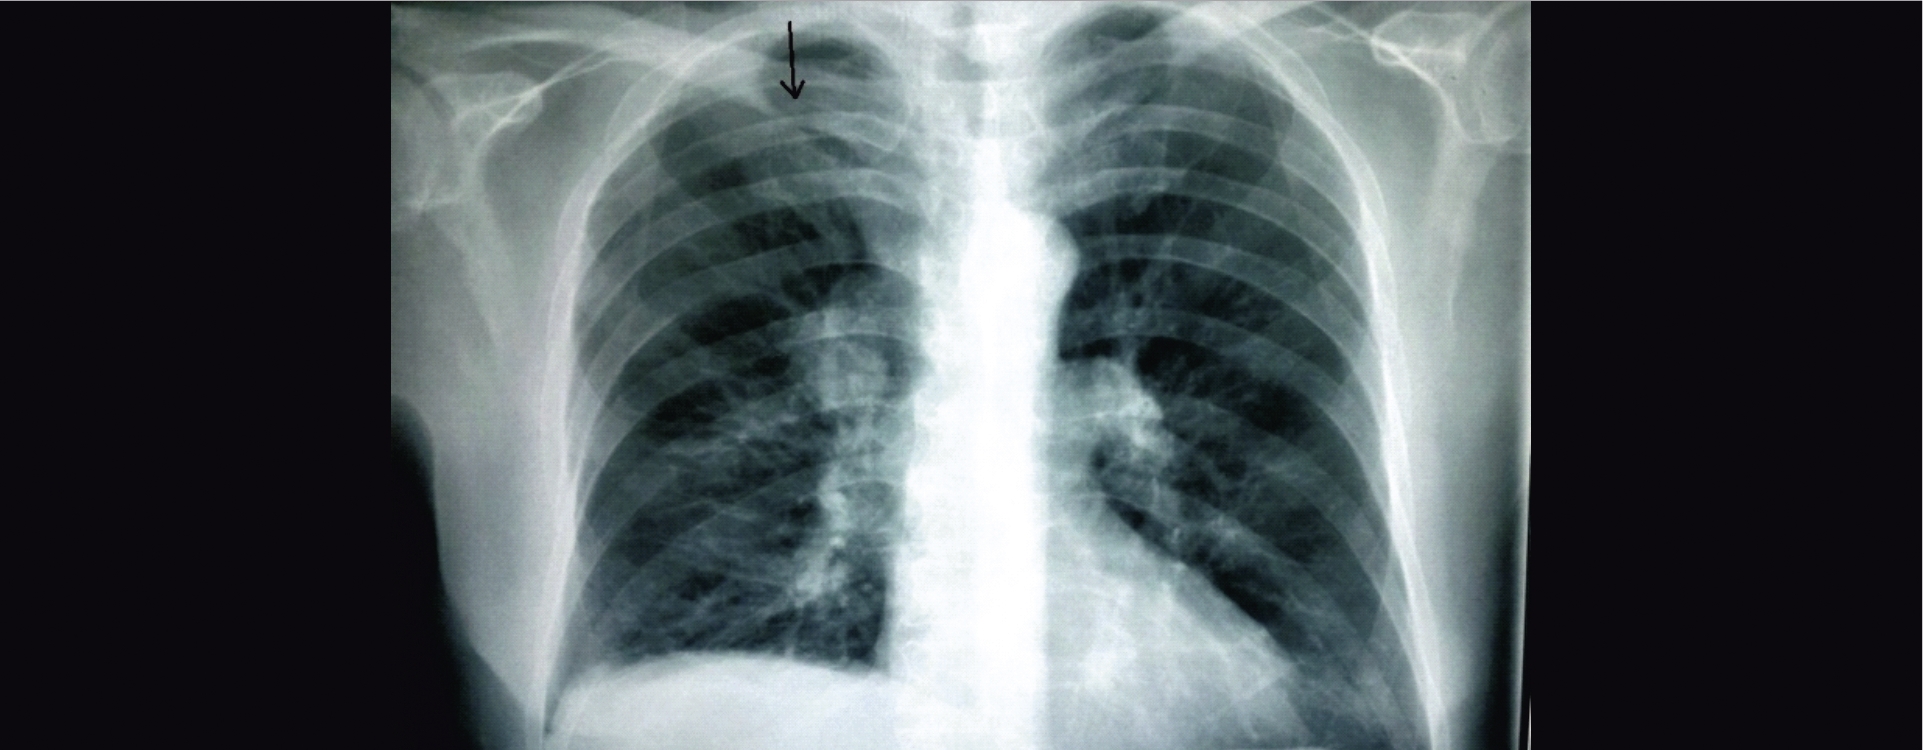

Компьютерная томография (КТ) грудной клетки с контрастным усилением от 30.11.2017 г.: в S3 правого легкого определяется мягкотканное образование округлой формы с лучистыми контурами, размерами 34×35×42 мм, без четких границ, прилежит к медиастинальной плевре и инвазирует ее. Перифокально отмечается утолщение внутридольковых и междольковых перегородок. В S10 левого легкого определяется мягкотканное образование с лучистыми неровными контурами, размерами 18×20 мм. В S8,9 правого легкого в кортикальных отделах плотные очаги до 5 мм. В обоих легких диффузно отмечаются участки повышенной воздушности легочной ткани без четких контуров. Внутригрудные, над-, подключичные, подмышечные лимфатические узлы не увеличены. В S8 печени определяется образование гиподенсивной структуры размерами 33×44 мм. Заключение: данных о тромбоэмболии легочных артерий (ТЭЛА) не получено. Образование (опухоль) верхней доли правого легкого с метастазами в нижнюю долю левого легкого. Эмфизема легких. Образование печени, требующее уточнения (рис. 1).

Рис. 1. КТ грудной клетки с внутривенным контрастированием при поступлении. А: в верхней доле справа визуализируется мягкотканное образование (маркер); Б: образование умеренно накапливает контрастный препарат в пределах 10HU (маркер), распространяется на клетчатку средостения и прилежит к верхней полой вене. В: в нижней доле слева отмечается другое мягкотканное образование (треугольная стрелка). Кроме того, в легких с обеих сторон визуализируются множественные парасептальные буллы (обведенная зона)